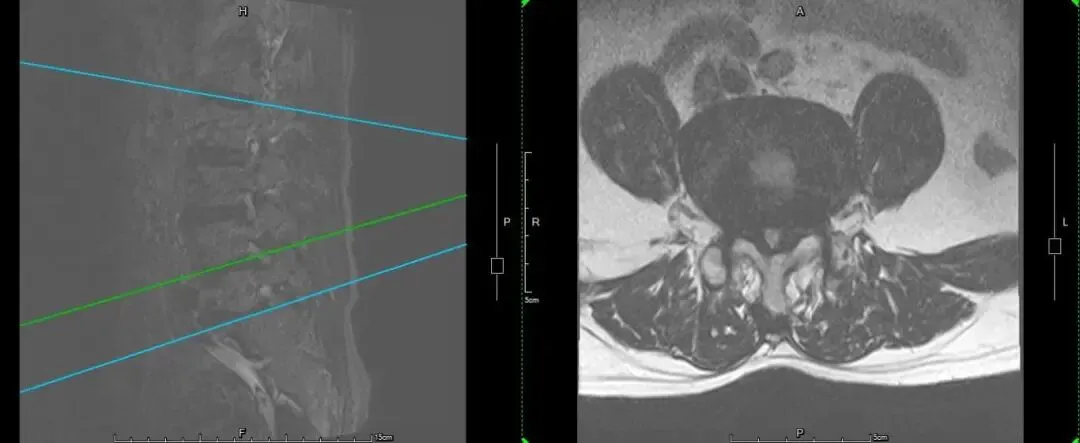

案例二:患者男,73岁,因“反复腰腿疼痛10年余,加重伴间歇性跛行2年”入院,入院诊断:1.腰椎椎管狭窄症2.腰椎滑脱3.腰椎间盘突出症。在全身麻醉下行后入路腰椎前柱融合术+腰椎间盘髓核切除伴椎板切除术+腰椎植骨术+L4/5脊髓神经根粘连松解术+2~3个椎骨融合或再融合+脊椎融合物置入术+腰椎脱位切开复位内固定术,术后恢复良好,患者及家属对治疗效果十分满意。